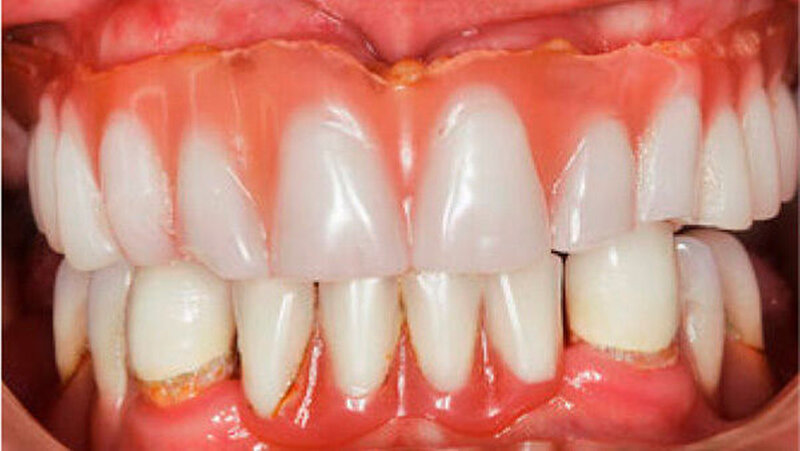

Aufgrund des anatomisch sehr ungünstigen Prothesenlagers war der Erhalt der Restbezahnung im Oberkiefer anzustreben. Nach Kariesexkavation und Wurzelkanalbehandlung konnten beide Zähne mit einer Wurzelstiftkappe versorgt und die alten Prothesen entsprechend umgebaut werden. Im Anschluss an die Meisterabformungen und an die Ausrichtung der Wachswälle wurden die Modelle schädelbezogen einartikuliert, und die Prothesenzähne nach ästhetischen und funktionellen Richtlinien aufgestellt. Eine bilateral balancierte Okklusionsbeziehung konnte umgesetzt werden. Im Oberkiefer wurde eine gerüstverstärkte Totalprothese hergestellt, die auf den beiden Wurzelstiftkappen 16 und 26 verankert war. Im Unterkiefer konnte die Patientin mit einer Totalprothese versorgt werden (Abb. 21 bis 23).